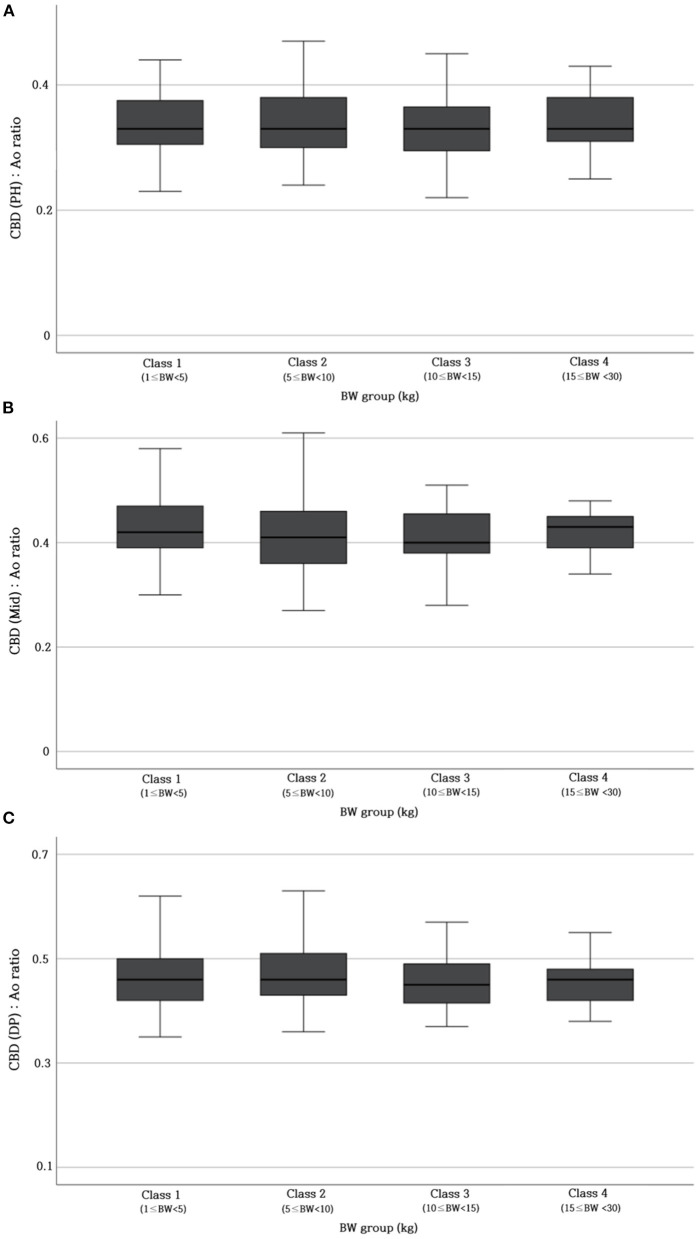

Table 2 provides the reference range of CBD: Ao ratio at three different sites. To verify whether this ratio was not affected by BW, the CBD: Ao ratio was compared between different BW groups. The ratio showed no significant difference at each site (p > 0.05) (Figure 4).

Table 2: Values of normal reference range of CBD: Ao ratio at PH, Mid, and DP level.

| Site | CBD: Ao ratio |

|---|---|

| PH | 0.34 ± 0.05 |

| Mid | 0.42 ± 0.06 |

| DP | 0.47 ± 0.06 |

Ao, abdominal aorta; CBD, common bile duct; DP, duodenal papilla; Mid, mid-portion; PH, porta hepatis.

Since the CBD diameter significantly differs according to BW, we attempted to devise a new indicator that can evaluate CBD diameter regardless of the BW. The aortic diameter has been used in ratio studies as a reliable landmark (ref. 20, ref. 21). Due to the tortuous course of the aorta, it may appear elliptical, leading to an overestimation of the actual diameter when using the major axis of the ellipse (ref. 22). Therefore, minor axis diameter of the aorta was measured in this study. We investigated whether the CBD: Ao ratio showed a constant value in different BW groups. The results confirmed that the CBD: Ao ratio remained constant between different BW groups (p > 0.05). Therefore, this new index could be used regardless of the BW.